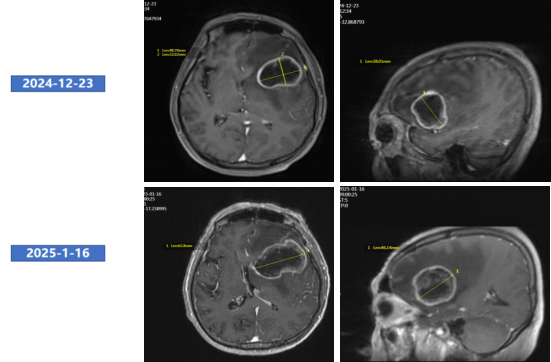

● 2024年12月23日头颅MRI平扫+增强:左侧额叶占位,考虑转移,不排除脑胶质瘤(最大直径71mm)。

头颅MRI增强(2024年12月23日)

● 2025年1月16日头颅MRI增强:左侧额叶占位,考虑转移,较前明显增大,中线移位。

头颅增强MRI

● 2025年3月20日头颅MRI增强:左侧额叶占位及周围水肿范围较2025年1月16日明显缩小。总体评效:PR(缩小53%)。

● 2025年6月19日复查头颅MRI增强:左侧额叶占位及周围水肿范围较2025年3月20日缩小。总体评效:PR(缩小70%)。

头颅增强MRI(左:2025年1月16日;中:2025年3月20日;右:2025年6月19日)